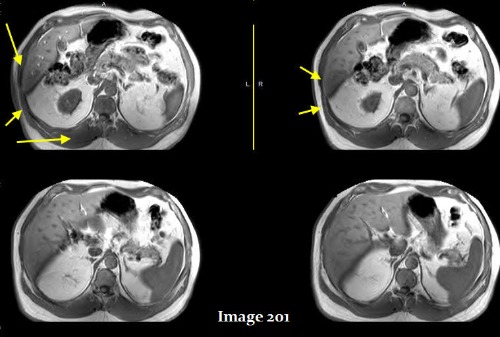

The yellow arrows in Image 201 display what type of MRI artifact?

A. Annefact

B. Aliasing

C. Dielectric effects

D. Fine line / FID